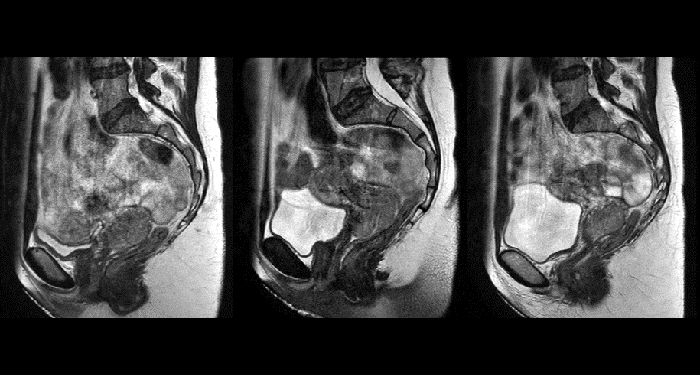

With its exceptional soft-tissue visualization capabilities and wide range of image contrasts, MRI has become a powerful tool to help more precisely define tumor boundaries. This is particularly important as it has been established that there is a high degree of uncertainty in target volume delineation, and it is even reported to represent the largest uncertainty in the entire radiotherapy process for most tumor sites**. Better visualization of the target area and nearby organs-at-risk is a key factor in enhancing target volume delineation. MRI’s expanding role also can be attributed to its functional imaging capabilities, which can inform both target characterization and treatment response.

MR-linac simulation package for Elekta Unity

The Philips Ingenia MR-RT simulation platform with MR linac simulation package is an ideal complement to Elekta Unity. With consistent workflows and image quality from MR simulation through to online MR guidance during radiation treatment, it will let you exploit the many similarities and synergies between Philips Ingenia MR-RT and Elekta Unity.